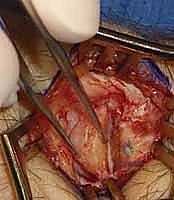

يفضل الأستاذ الدكتور محمد هطيف النهج الجراحي المفتوح (Open Approach) في العديد من الحالات، خاصة عندما تكون هناك حاجة لإجراءات متزامنة (مثل ترقيع العظم الزورقي أو ترميم الأربطة). يوفر النهج المفتوح رؤية تشريحية مباشرة وممتازة، مما يقلل من احتمالية إصابة الهياكل الحساسة.

- الشق الجراحي: يُجري الدكتور هطيف شقاً جراحياً دقيقاً (حوالي 3-4 سم) على الجانب الكعبري للرسغ، متمركزاً فوق الحيز الظهري الأول (First Dorsal Compartment).

- حماية الأعصاب (الخطوة الأهم): يتم تحديد العصب الكعبري السطحي (Superficial Radial Nerve) وفروعه بدقة متناهية باستخدام تقنيات الجراحة الميكروسكوبية، وإبعاده برفق لحمايته من أي أذى. إصابة هذا العصب قد تؤدي إلى ألم مزمن أو خدر دائم.

- الوصول إلى المفصل: يتم فتح محفظة المفصل (Joint Capsule) لكشف الزائدة الإبرية الكعبرية والقطب البعيد للعظم الزورقي. يتم فحص مدى تآكل الغضاريف بالرؤية المباشرة.

- عملية الاستئصال (Osteotomy): باستخدام أزاميل دقيقة جداً (Osteotomes) أو مناشير جراحية صغيرة، يقوم الدكتور هطيف بإزالة الجزء المتآكل من الزائدة الإبرية.

- القاعدة الذهبية للدكتور هطيف: يتم استئصال حوالي 3 إلى 4 مليمترات فقط، وبزاوية محددة، مع الحرص الشديد على عدم تجاوز 6 مليمترات. لماذا؟ لأن إزالة أكثر من ذلك ستؤدي إلى قطع منشأ الرباط الكعبري الزورقي القبطي (RSC ligament)، مما يتسبب في انزلاق وانخلاع عظام الرسغ (Carpal Instability).

- الكي والإغلاق: بعد التأكد من إزالة كل الحواف العظمية الخشنة وغسل المفصل، يتم إغلاق محفظة المفصل بعناية، ثم خياطة الجلد بغرز تجميلية دقيقة لتقليل الندبات.